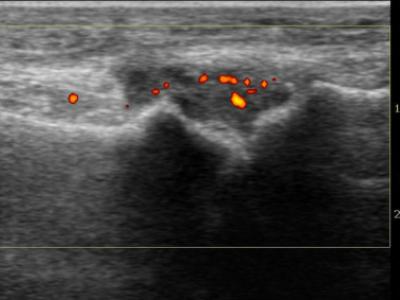

"Dry Synovitis" exist in juvenile arthritis pts? Study of 12 DS pts, says its different from Poly #JIA; onset 6.1 yrs, w/ polyarthritis, no palpable swelling, progressive LOM/contractures, neg ESR/CRP/RF/CCP, +MRI synovitis w/ osteochondral involvement.https://t.co/tL2G7QKBL4 https://t.co/k4QoAmTGYA